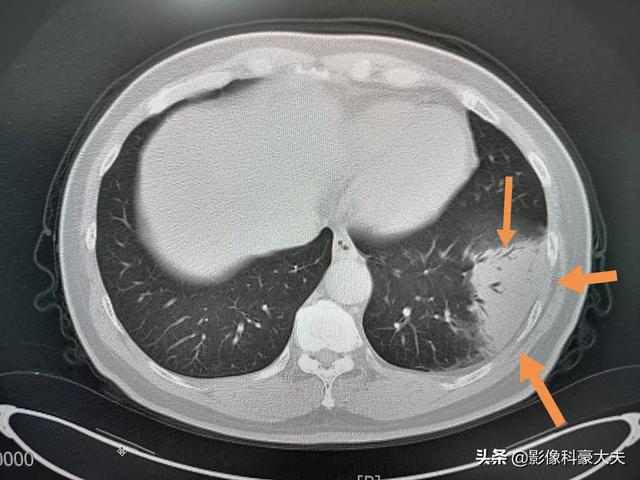

Cet homme d'âge moyen, qui toussait et avait de la fièvre depuis trois jours, présentait au scanner une pneumonie inférieure gauche, répartie le long du sous-segment, avec une densité relativement élevée (pas d'ombre de verre dépoli), et des signes d'insufflation bronchique étaient observés du côté hilaire des poumons, accompagnés d'une augmentation de la numération sanguine, ce qui en faisait une pneumonie banale, et non un coronavirus.

Il a été traité avec des antibiotiques et s'est considérablement résorbé au bout de 9 jours :

2. avec des caractéristiques d'imagerie de pneumonie :Cela signifie qu'il y a des changements inflammatoires dans les poumons, présentant de multiples petites ombres en taches et des changements interstitiels, qui sont évidents dans les bandes externes des poumons, et même des changements tels que de multiples ombres en verre dépoli et des ombres d'infiltration dans les deux poumons. Vous vous demandez peut-être pourquoi il y a des changements d'imagerie dans les poumons après une infection. C'est principalement parce qu'une fois que le virus a envahi les poumons, il peut provoquer une congestion et un œdème dans les poumons, qui se traduisent par des ombres de haute densité sur la radiographie ou la tomodensitométrie.

②La tomodensitométrie thoracique peut suggérer de multiples ombres parcellaires et des changements interstitiels au stade précoce, et elle est évidente dans les bandes extrapulmonaires, et l'examen ultérieur développe de multiples ombres en verre dépoli et des ombres d'infiltration dans les deux poumons, et dans les cas sévères, des lésions pulmonaires solides apparaîtront.

②. Le thorax présente les caractéristiques d'imagerie d'une pneumonie.

Au stade initial, elle présente de multiples petites taches et des changements interstitiels, qui peuvent évoluer vers de multiples taches en verre dépoli et infiltrées dans les deux poumons et, dans les cas les plus graves, des changements solides dans les poumons peuvent se produire, ce qui donne ce que l'on appelle communément les "poumons blancs".